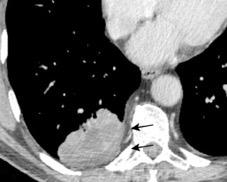

Signo de la Pleura separada “Split pleural sign”

Capas pleurales de grosor uniforme realzadas por el contraste

No específico de empiema. Indica “exudado”. 68% de pacientes con empiema pleural.

Capas pleurales de grosor uniforme

Realce grasa extrapleural (30%)

> Grasa Extrapleural. (60-80%)

Kraus GJ. Split pleural sign. Radiology 2007